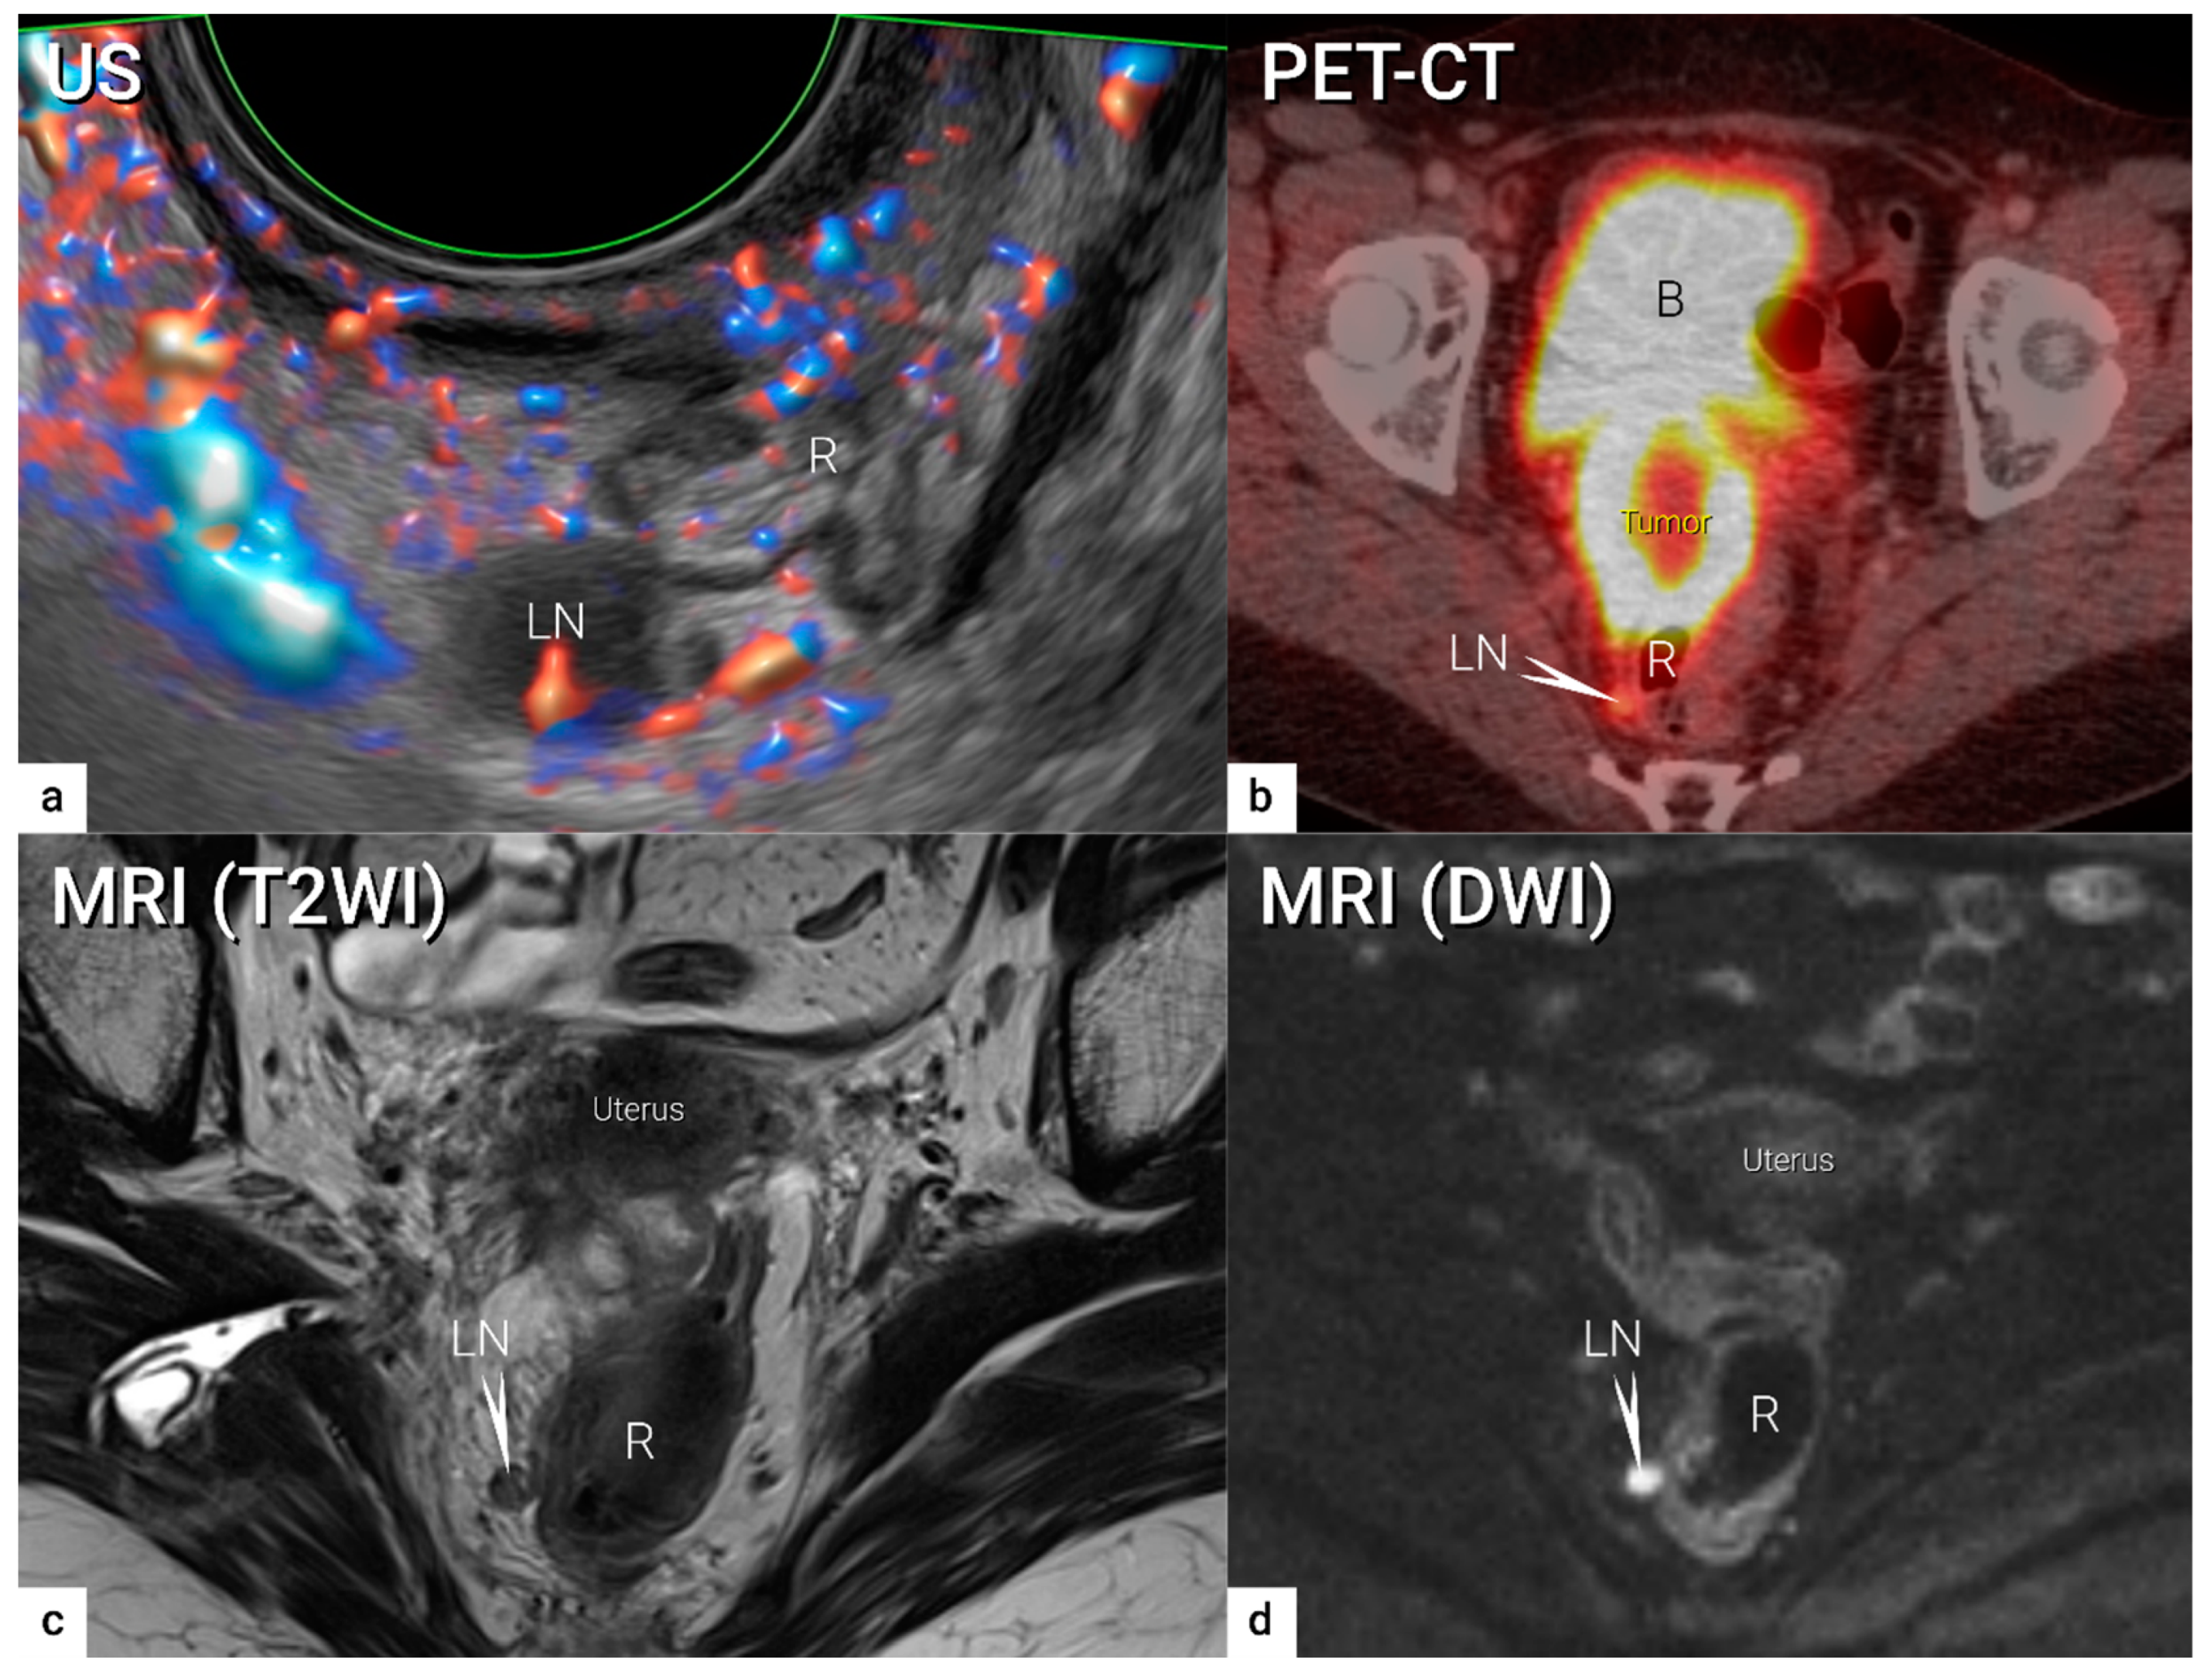

| N1 | IIIC1 | Regional lymph node metastasis to pelvic lymph nodes only | US: hypoechogenic rounded lymph node without preservation of typical architecture (loss of the nodal core-sign), inhomogeneous echogenicity due to cystic necrosis and calcifications, capsular interruption, grouping of metastatic lymph nodes and others. Hilar flow may still be preserved in a partial nodal involvement with or without transcapsular vascularisation (vessels penetrating the cortex from outside), the latter are usually found in an advanced stage of infiltration. MRI: lymph nodes with maximum transverse diameter>10 mm; capsule irregularity, rounded (as opposed to oval) shape, inhomogeneous signal with signs of necrosis on T2W images (MRI), restricted diffusion (DWI) or increased FDG-avidity (PET-CT) |

4. Nodal and distant diagnostic workup